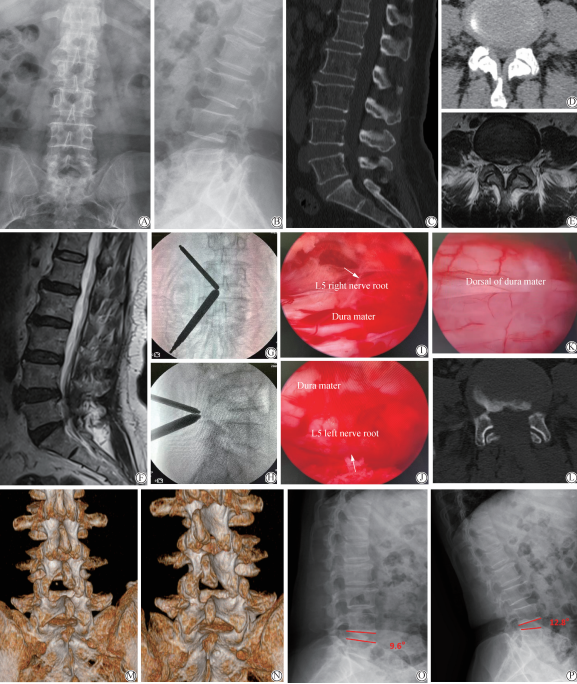

图1 患者,女性,59岁,腰疼伴双下肢后外侧麻木、疼痛2年,加重2个月。

A-B: pre-operation X-ray: no indication of instability and spondylolisthesis of L4 / 5;

C-F: pre-operation CT and MRI: bilateral lateral recess stenosis in L4 / 5,with bilateral L5 nerve roots compressed;

G-H: left approach; localizing and channel establishment;

I-K: vertebral canal decompressed; bilateral L5 nerve root relaxation without compression; dorsal dural sufficiently decompressed;

L-N: post-operation CT revealed bilateral medial facet joint resection, lateral recess sufficiently decompressed. The left facet joint was largely preserved and the right facet was intact.

O-P: post-operation for 12 months, lumbar radiographs in hyperflexion and hyperextension showed no L4 / 5 instability; CT:computed tomography; MRI:magnetic resonance imaging